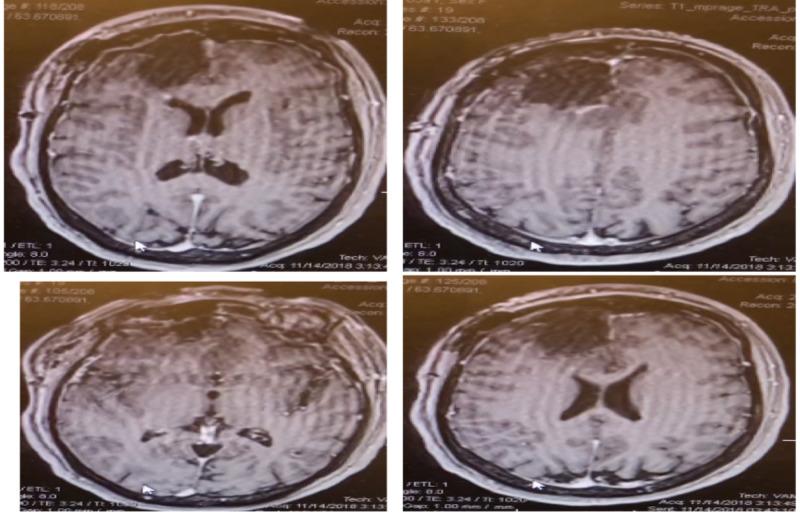

Primary angiitis of the central nervous system (PACNS) is a rare form of vasculitis and is confined entirely to the central nervous system (CNS)without systemic involvement. We report a rare case of PACNS in a 39-year-old female with new onset seizures and a right frontal enhancing mass. Initially the patient was thought to have a high-grade glioma and thus underwent a right frontal craniotomy for resection of right frontal mass. Intraoperatively, two fresh tissue samples were sent for intraoperative consultation. Sample 1 showed predominantly necrotic tissue and scant glial cells while sample 2 revealed glial tissue favoring gliosis versus low-grade neoplasm with necrosis and a few acute inflammatory cells. Final pathological diagnosis was consistent with PACNS. Postoperatively, the patient recovered well from surgery with no neurological deficits and was discharged on postoperative day 3. Two weeks after surgery the patient was started on cyclophosphamide and prednisone by Rheumatology. At one month follow up, the patient remained asymptomatic and seizure free.

中枢神经系统原发性血管炎(PACNS)是一种罕见的血管炎形式,完全局限于中枢神经系统(CNS),无全身受累。我们报告一例罕见的PACNS病例,患者为39岁女性,新发癫痫,右侧额叶有强化肿块。最初,该患者被认为患有高级别胶质瘤,因此接受了右侧额叶开颅手术以切除右侧额叶肿块。术中,送了两份新鲜组织样本进行术中会诊。样本1主要显示坏死组织和少量胶质细胞,而样本2显示胶质组织,倾向于胶质增生而非伴有坏死和少量急性炎症细胞的低级别肿瘤。最终病理诊断与PACNS一致。术后,患者手术恢复良好,无神经功能缺损,术后第3天出院。术后两周,风湿科开始让患者服用环磷酰胺和泼尼松。随访1个月时,患者无症状且无癫痫发作。